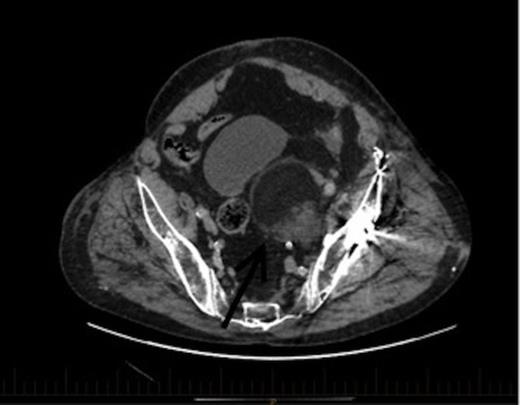

An axial section of the CT demonstrating a 6.7x6cm.3x7.3cm left pelvic lesion adjacent to the trauma site. Arrow denotes the EMH lesion

A CT scan demonstrated a 6.7x6.3cmx7.3cm well-defined left pelvic mass immediately medial and adjacent to the left acetabulum compressing the bladder and the iliac vessels. The mass was heterogeneous in density comprising of both muscle and fat with no calcifications. He underwent a repeat staging-CT, MRI, whole body thallium scan, and a CT-guided biopsy. The MRI scan confirmed a lobulated well-circumscribed mass with a heterogeneous T1 and T2 appearance. Areas of hyperintensity reported on CT corresponded to fatty components within the mass, while the rest of the mass appeared relatively hypointense to skeletal muscle, and was thought to be consistent with a liposarcoma. The Single Photon Emission Computed Tomography (SPECT) scan demonstrated low-grade activity in the mass and the staging-CT did not reveal any signs of malignancy. A confirmatory CT-guided biopsy however diagnosed the mass as EMH tissue, while a CT angiogram demonstrated no external compression of the iliac vessels.

CT coronal view of the lesion demonstrating compression of the bladder. Arrow denotes the EMH lesion

This patient was subsequently discussed at a multidisciplinary meeting, where it was decided that in view of the urinary symptoms and his high operative risk, the mass should be treated with CT-guided radiofrequency ablation using a multi-lined electrode. However, the patient declined treatment and was temporarily lost to follow up after moving interstate. Two years later, he presented to the hospital with bowel obstruction secondary to an incisional lumbar hernia, and the follow up CT scan (Figures 2 and 3) revealed no increase in the size of the mass, and repeat biopsy re-confirmed the presence of EMH. His urinary symptoms remained stable.